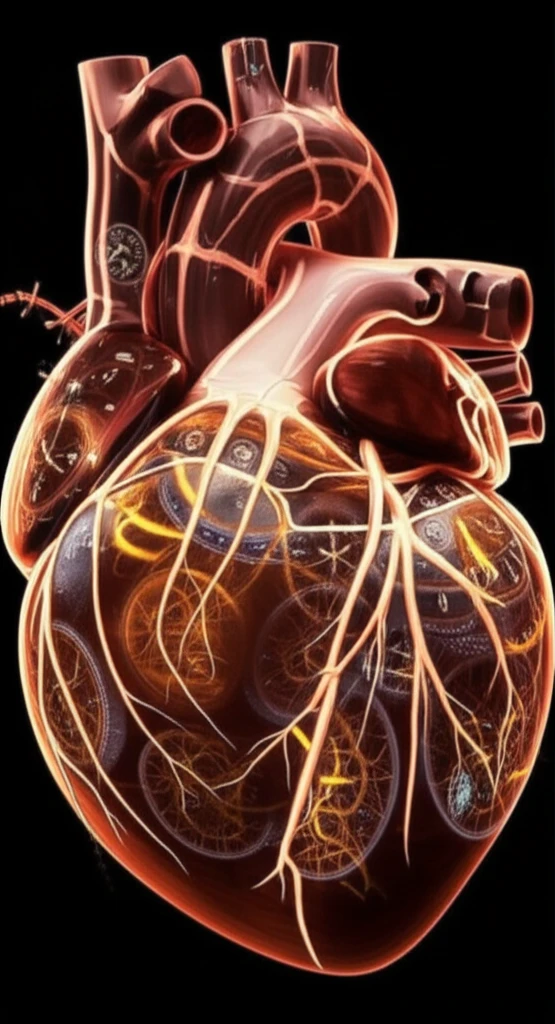

Dilated cardiomyopathy (DCM), a condition where the heart's ability to pump blood effectively is compromised, poses significant challenges in healthcare. Predicting which patients are most at risk and tailoring treatments accordingly is critical. Traditionally, factors like age, overall physical condition, and the heart's ejection fraction have been considered. However, recent studies suggest that assessing the heart's synchronicity—how well its different parts contract and relax together—may offer deeper insights.

Heart specialists are focusing on cardiac dyssynchrony, where the heart's chambers do not beat in a coordinated manner. Both systolic dyssynchrony (when the heart contracts) and diastolic dyssynchrony (when it relaxes) can impact cardiac performance. While systolic dyssynchrony is a known risk factor, the role of diastolic dyssynchrony is less understood. New research aims to clarify how both types of dyssynchrony affect patient outcomes in DCM.

By using advanced imaging techniques like gated SPECT MPI (Single Photon Emission Computed Tomography Myocardial Perfusion Imaging), doctors can now measure the heart's mechanical function with greater precision. This non-invasive approach allows for detailed analysis of both systolic and diastolic phases, potentially unlocking new ways to predict and manage heart failure.